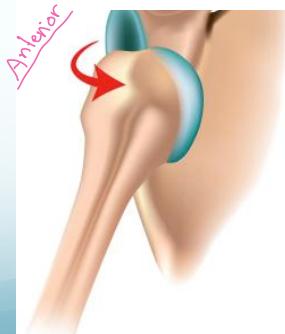

Anterior Shoulder Dislocation

Definition: The humeral head lies anterior to the glenoid

- Forced abduction, external rotation:

- Throwing/catching a ball

- Hitting ball with racket

- Forced in weight-lifting

- A fall on the backward stretching hand